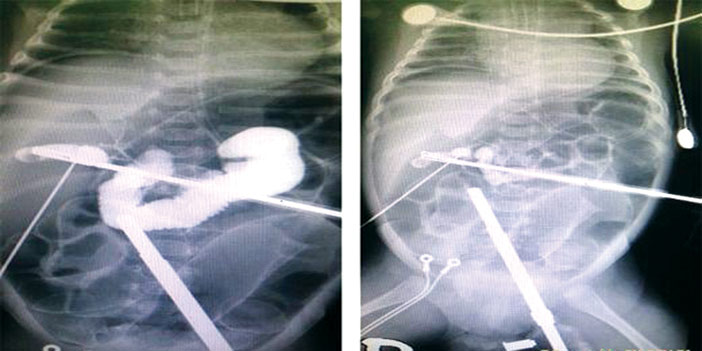

أجرى مستشفى الولادة والأطفال ببريدة، ممثلاً بوحدة المناظير والجهاز الهضمي بقسم جراحة الأطفال، أول عملية جراحية صبغة تشخيصية للقنوات الصفراوية بالمنطقة لطفل عمره 60 يوماً، حيث تم إجراء العملية عن طريق المنظار الخارجي، وتم حقن الصبغة داخل القنوات الصفراوية للتأكد من عدم وجود انسداد خلقي. العملية تمت بقيادة رئيس قسم وحدة مناظير الجهاز الهضمي الاستشاري د. عبدالعزيز الحربي، بمشاركة رئيس القسم الاستشاري د. لوكا شامبوغ، ود. سامر باقي اخصائي جراحة الأطفال بالمستشفى. مدير مستشفى الولادة والأطفال عبدالعزيز الفوزان، أوضح بأن هذه العملية أول عملية من نوعها في منطقة القصيم، وأن الطفل بصحة جيدة.. مبيناً بأن المستشفى سيعمل على تطوير جراحات التخصصات الطبية الأخرى، مما سيسهم في توفير أفضل البرامج العلاجية للمرضى.